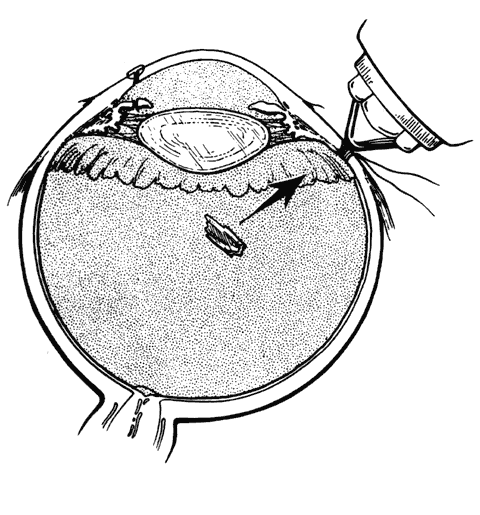

hemorrhage, retinal breaks, and retinal detachment. SUBLUXATION OR DISLOCATION OF THE LENS Minor degrees of subluxation should be suspected when phakodonesis or iridodonesis is noted. Zonular rupture is certain if there is vitreous prolapse into the anterior chamber. In the absence of cataractous changes and related visual impairment, treatment is not indicated. A subluxated, cataractous lens can be removed by aspiration-irrigation or phacofragmentation through a limbal incision, but complications may occur, including posterior dislocation of the lens or lens fragments, vitreous prolapse and incarceration, and vitreous aspiration with resultant vitreous base traction and retinal tear formation. Also, visualization of the anterior vitreous by coaxial illumination is poor compared with fiberoptic endoillumination. These problems make pars plana lensectomy an attractive alternative. Bimanual techniques permit fixation and simultaneous removal of the lens by the vitreous suction-cutter, if the lens is soft, or phacofragmentation if it is sclerotic (Fig. 1A). Posteriorly dislocated fragments can be removed safely, with minimal vitreous traction, using the same incisions and instruments (see Fig. 1B). With endoillumination, prolapsed and juxtalenticular vitreous is readily identified and excised with the vitrectomy probe. Without question, pars plana lensectomy is the preferred method for removing a completely dislocated lens. The technical aspects of dislocated lens and lens fragment removal are described elsewhere in these volumes. VITREOUS HEMORRHAGE Blood in the vitreous may come from tears in the iris, ciliary body, choroid, or retina. Hemorrhage from choroidal ruptures accumulates beneath the neurosensory retina; it then passes through the retina into the vitreous without necessarily causing a retinal break. Regardless, it is important to assume that a retinal break is present until proved otherwise. Vitrectomy is indicated for vitreous hemorrhage caused by ocular contusion when a retinal detachment is suspected because of sudden additional loss of vision, when a retinal detachment is detected through a window in the hemorrhage, when a large retinal break or retinal detachment is diagnosed by ultrasound, or when there is no improvement after a reasonable period of observation. Preoperative contact A-scan and B-scan ultrasonography is helpful for detecting posterior vitreous detachment and differentiating it from retinal detachment. It is dangerous, however, to rely completely upon the accuracy of ultrasound. The presumed posterior hyaloid should be approached with caution until it can be identified with certainty. A standard three-port vitrectomy technique is preferred for nonclearing vitreous hemorrhage. Initially, a central core of opaque vitreous is removed, beginning sufficiently close to the lens that the tips of the cutter and endoilluminator can be visualized. The excision is carried posteriorly, removing successive layers of hemorrhagic and fibrinous vitreous, until the anticipated plane of the posterior hyaloid is approached. A constant surveillance is maintained for a gray membrane containing radially oriented vessels (undiagnosed detached retina). A small opening is made in the detached posterior hyaloid, through which unclotted blood is aspirated by use of active suction from a soft-tipped cannula. Once the retina has been visualized, it is best to remove as much retrohyaloid blood as possible to prevent dispersion into the vitreous cavity with consequent loss of visual control. If the posterior vitreous cortex is not detached, it can be separated from the retina by gentle suction with a soft-tipped cannula at the edge of the optic disc. The elevated cortex is penetrated with a hooked needle or myringotomy blade, creating a window through which a pick is introduced to enlarge the area of cleavage. With the plane between hyaloid and retina established, the surgeon attempts to remove the entire cortical vitreous except for the firmly attached portion at the anterior vitreous base. Cortex that does not separate with gentle manipulation is isolated from surrounding vitreous to eliminate traction on the retina. It is important to remove the cortical vitreous from areas adjacent to retinal breaks. Failure to do so may result in subsequent tangential traction and retinal detachment. A scleral buckle should be considered if retinal breaks cannot be freed from surrounding vitreous cortex. The placement of sclerotomies close to the 3 o'clock and 9 o'clock positions facilitates maximal excision of the hemorrhagic anterior vitreous skirt, thereby improving visualization of the peripheral retina and pars plana. With use of coaxial illumination and scleral depression, the peripheral vitreous on the temporal side of the globe is trimmed with the cutter placed in the temporal sclerotomy, reaching both the superior and inferior quadrants, after which it is transferred to the nasal sclerotomy, and the process is repeated. The fiberoptic endoilluminator may damage the lens if used internally to illuminate the peripheral vitreous on the opposite side of the globe. However, the cone of light from the probe may be directed through the cornea to augment or replace the coaxial light source. Hemorrhagic retrolenticular vitreous can be stripped from the posterior capsule of the lens by gentle aspiration into the cutting port followed by withdrawal of the probe and simultaneous activation of the cutting mode. This technique is dangerous in young children because the retrolenticular vitreous is adherent to the lens, which is sufficiently pliable for aspiration into the port with consequent cataract formation. When the lens is clear, the process of removing peripheral and retrolenticular vitreous is less important than preserving lens integrity in most cases. It is important to expose the peripheral retina and vitreous base because most retinal breaks caused by ocular contusion are located in this area.2 All retinal breaks should be treated. Endolaser is used for posterior breaks, whereas peripheral breaks are treated with indirect laser assisted by scleral depression or transscleral cryoretinopexy. Cryotherapy is preferred when residual opaque vitreous partially obscures the targeted break. Encircling scleral buckles are not necessary after vitrectomy for nonclearing vitreous hemorrhage caused by ocular contusion when a clear view of the fundus periphery reveals no peripheral retinal tears or signs of traction, such as vitreous base avulsion. Similarly, the support of a buckle is usually not needed for treated retinal breaks without retinal detachment. A local scleral buckle should be used when there is residual traction on a posterior break. The peripheral retina should be supported by an encircling scleral buckle when traction on breaks in the oral zone persists or the periphery is poorly visualized because of residual opaque vitreous. RETINAL BREAKS Retinal breaks are created at the time of nonpenetrating blunt injuries3 in 10% to 20% of eyes.3–6 Retinal dialyses are most frequent2–6 and are most often found in the lower temporal (Fig. 2) and upper nasal periphery (Fig. 3).2 Large irregular breaks at the point of impact of blunt trauma are less common but are equally characteristic of nonpenetrating injuries (see Fig. 3).2,7,8 Horseshoe and opercular tears of the equatorial retina (see Fig. 3) are associated with the more characteristic breaks in 25% of eyes.2 Small round holes in atrophic retina at the point of traumatic impact and macular holes (see Fig. 3) are infrequently observed after ocular contusion.2,8 Prophylactic treatment of most traumatic retinal breaks is indicated. Breaks at the point of impact are one exception because they are frequently self-sealing. The surrounding necrotic retina and choroid often unite in a common scar without prophylaxis. It is wise, however, to treat these large tears when scleral depression reveals a slight elevation and movement of their edges and the surrounding retina. Traumatic macular holes also are not treated to prevent additional loss of central vision. They seldom cause retinal detachments when left alone. RETINAL DETACHMENT Although retinal breaks are produced at the time of injury, the retinal detachment may be delayed for months to years because the vitreous gel acts like a tamponade until liquefaction occurs.2 The detachment is typically shallow and slowly progressive because the large volume of vitreous gel in younger eyes prevents bullous retinal elevation as commonly seen in older patients with nontraumatic retinal detachments. Careful preoperative and intraoperative indirect ophthalmoscopy with scleral depression is the key to successful treatment of detachments caused by traumatic retinal dialyses. Small dialyses at the vitreous base borders are difficult to identify, particularly in the upper nasal quadrant where they frequently occur. Breaks of the pars plana epithelium, at the anterior vitreous base border, are less apparent than retinal tears at the posterior edge of the vitreous base. Small dialyses are closed by scleral depression, in which case they are more easily seen on the lateral slopes of the indentation than on its crest. Transscleral cryotherapy is diagnostically helpful. It is not unusual to discover breaks at the vitreous base border for the first time when the edges of the tear are whitened by freezing a suspicious area. It is prudent to treat the entire zone of vitreous base pathology with cryotherapy under direct visual control (see Fig. 3). In this way, treatment of all retinal breaks is assured. The anterior, posterior, and lateral limits of the treated zone are carefully localized and supported by a broad scleral buckle to relieve traction on the entire area. The posterior edge of the dialysis should fall on the crest of the buckle, which must be sufficiently broad to support the anterior edge as well, thereby preventing a recurrent detachment due to anterior leakage. Segments of grooved solid silicone tires are used together with an encircling band, which is positioned on a great circle of the globe to minimize anterior or posterior migration of the buckle. The band is tightened to ensure permanent indentation of the tire segment, but a high encircling buckle is avoided because it promotes posterior gaping or “fish-mouthing” of the dialysis. The band is anchored by a nonabsorbable mattress suture or scleral belt loop in each of the quadrants not occupied by the tire segment. The retinal detachment is often shallow. To avoid retinal perforation or incarceration, subretinal fluid is released through a sclerotomy in an area of sufficient retinal elevation determined by intraoperative indirect ophthalmoscopy with scleral depression. Viewed in profile, the scleral indentation helps gauge the distance between retina and retinal pigment epithelium. To avoid retinal incarceration and blowout, sclerotomies posterior to the buckle should be securely closed after the release of fluid, particularly if additional manipulation of the buckle or an intravitreal gas injection is anticipated. Retinal dialyses in the lower temporal quadrant are often very large, with gaping posterior edges located well behind the equator (see Fig. 2). They are caused by injuries impacting the lower temporal portion of the globe that result in the dissolution and disappearance of retinal tissue.8 In contrast to nontraumatic giant retinal tears with rolled-over retina, they respond favorably to scleral buckling without vitrectomy. A scleral buckle is indicated for smaller dialyses that can be closed with an explant of reasonable size. Very large breaks, as illustrated in Figure 2, are best treated with vitrectomy, gas tamponade, and laser, as recommended for nontraumatic giant retinal tears, rather than with a very large scleral buckle. Traumatic horseshoe and opercular tears are treated with scleral buckling surgery, as are similar nontraumatic retinal breaks. Likewise, traumatic macular holes in detached retina are managed by vitrectomy, internal drainage, and gas tamponade. The use of laser in such cases is controversial but is probably indicated for recurrent detachments and eyes with pre-existing poor central vision due to other traumatic macular damage. |